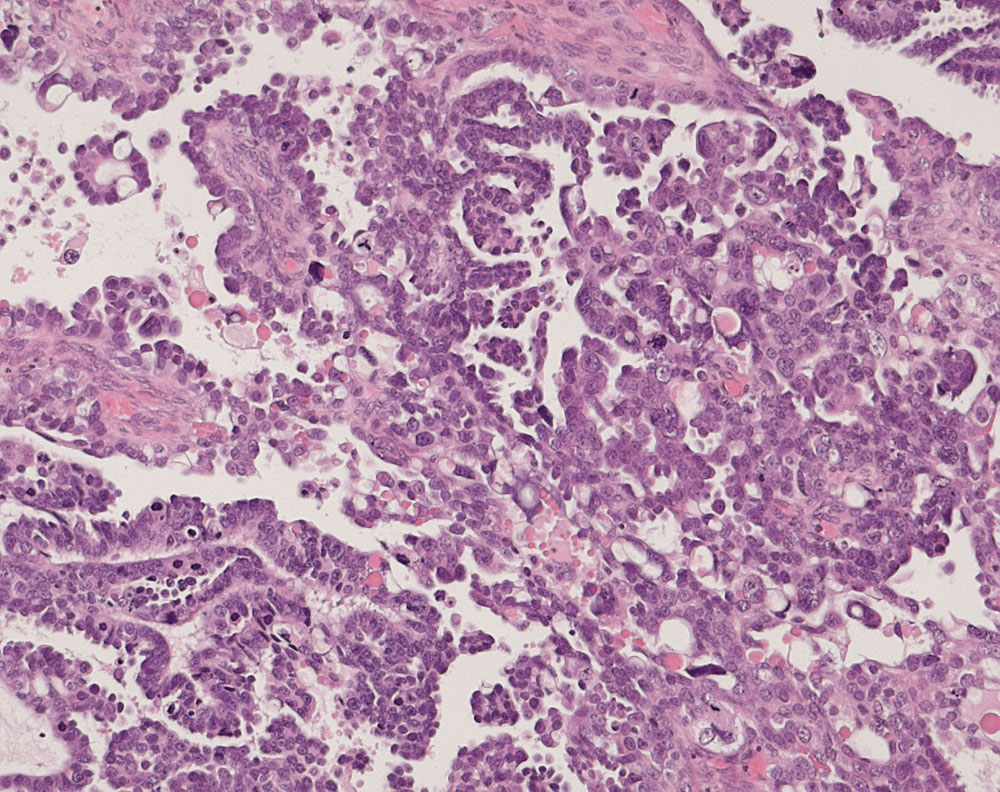

PathoPic ID 10934 - seröses Ovarialkarzinom high grade

seröses Ovarialkarzinom high grade

maligner Tumor

Ovar

Genitalorgane, weiblich

Papillärer Tumor bestehend aus stark atypischen und vereinzelt bizarren pleomorphen Tumorzellen mit starken Kerngrössenschwankungen. Mehrere, teils

atypische Mitosen und Apoptosen.

Verdacht auf Ovarialkarzinom (CA125 > 2000u/l). CT: Vergrösserte Ovarian beidseits. Maligner Pleuraerguss Adenokarzinom.

Histologie

100